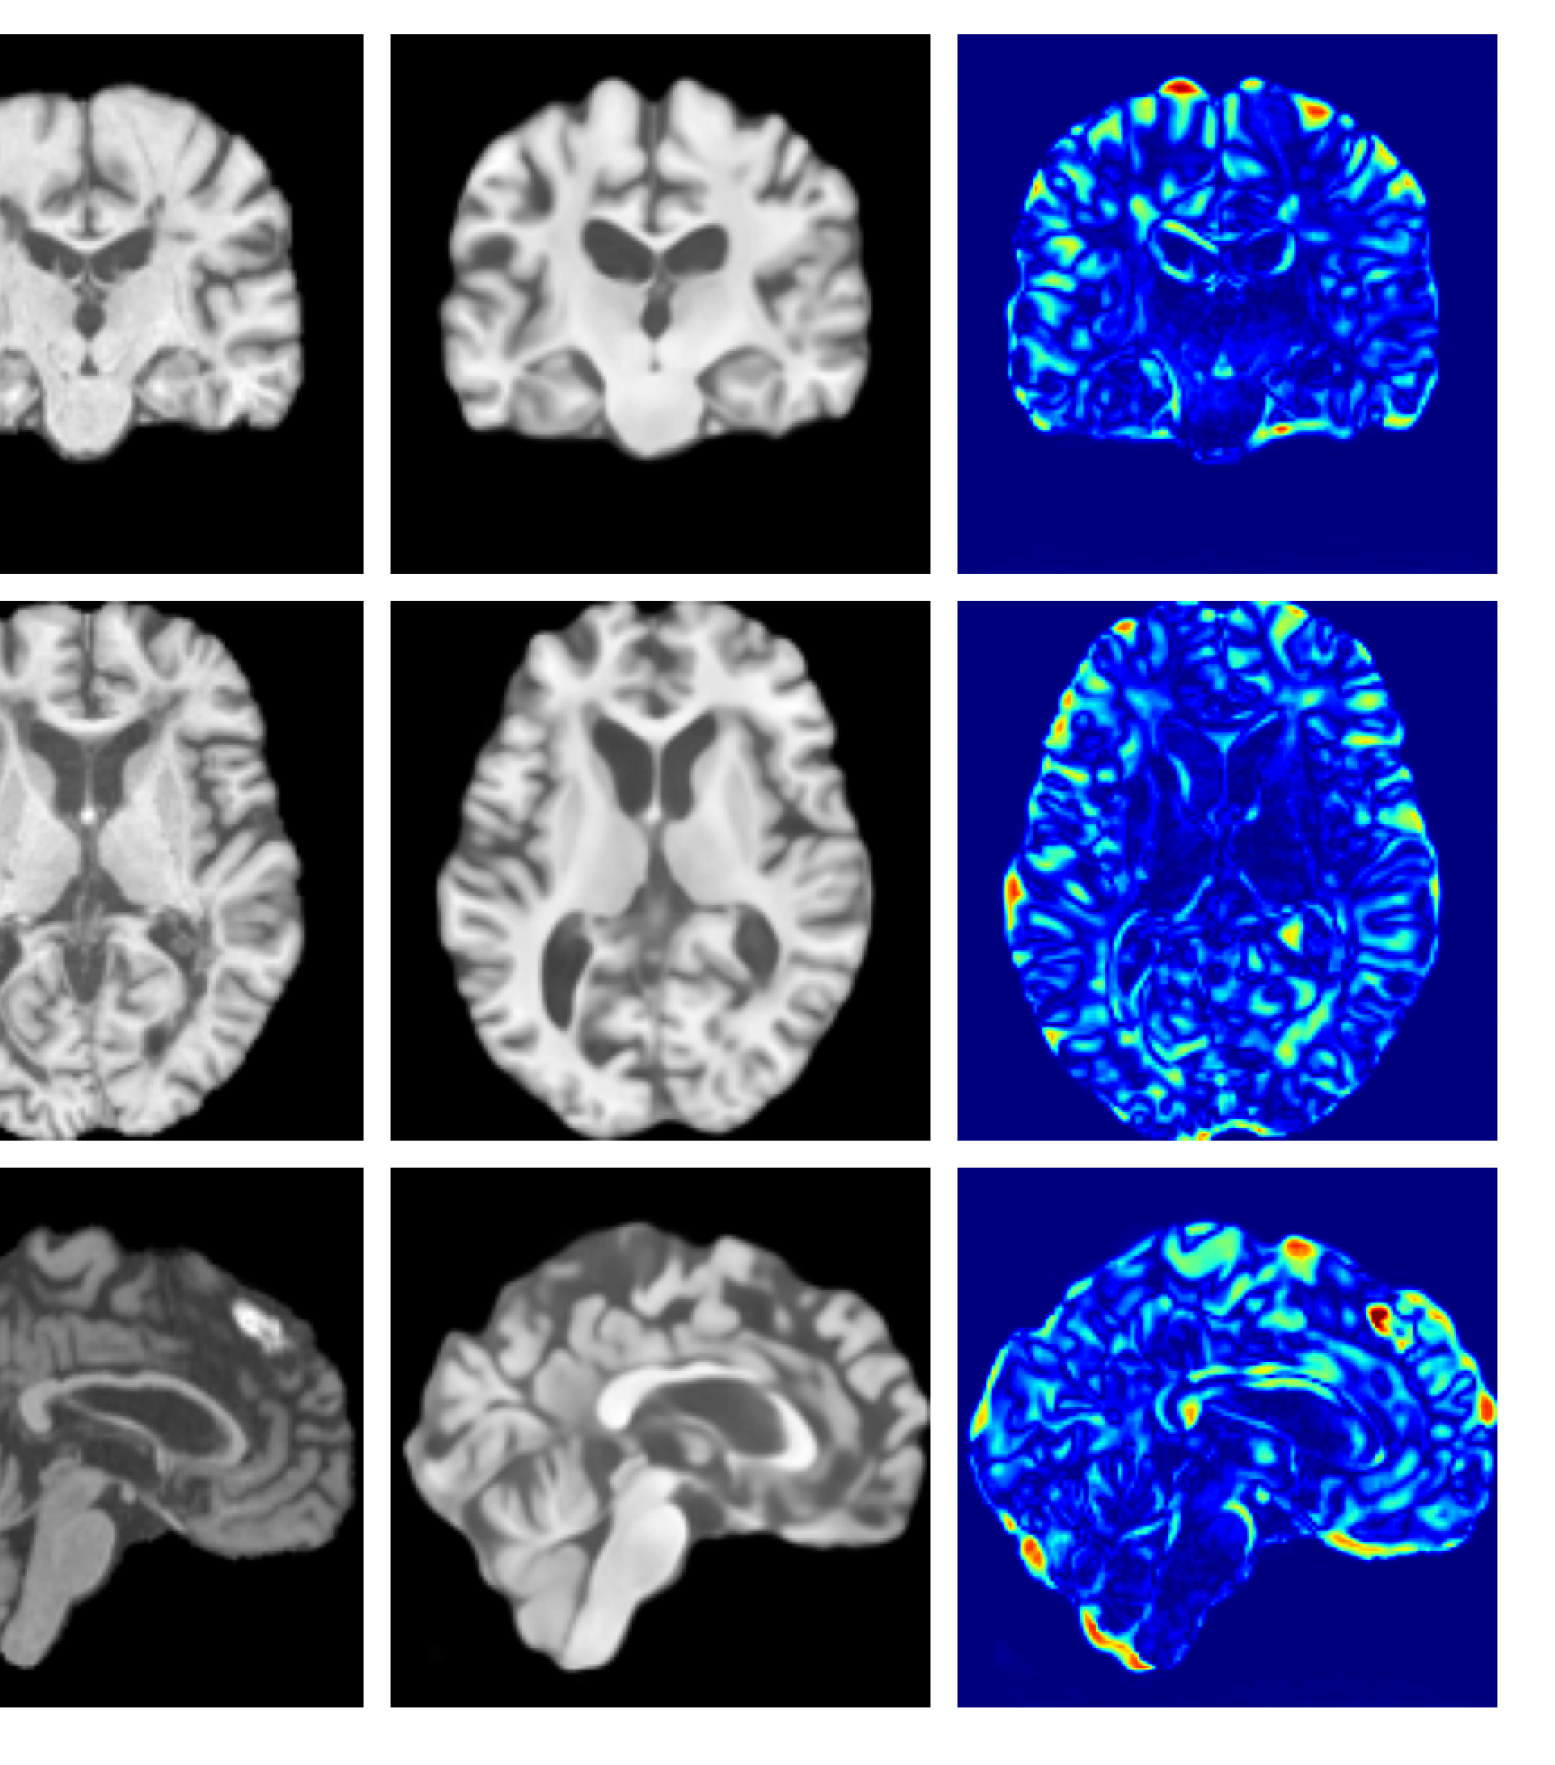

Figures 8 and 9 are enlarged versions of Figures 3 and 4 respectively, with the latter now including results from all compared methods. Figure 10 provides example reconstructions and anomaly maps for an AD subject from the ADNI disease cohort.

Refer to caption

Figure 10: Example reconstructions and anomaly maps for an AD sample from the disease cohort of the ADNI dataset. We expect to see some inpainting of atrophied tissue whilst retaining the defining characteristics of the individual sample.